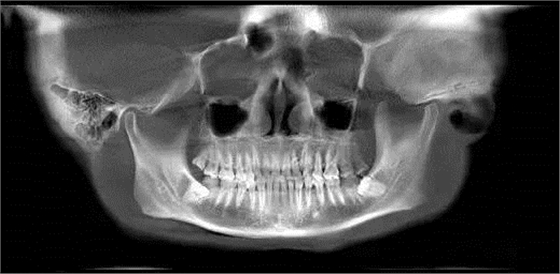

第四圖:上頜竇發(fā)育不足,上頜竇底骨高度充裕,通常頰側(cè)骨壁超級厚,看下圖2.臨床上種植常不需要提升措施。(如需提升,切記頰側(cè)骨厚度過大,開窗的困難性劇增)